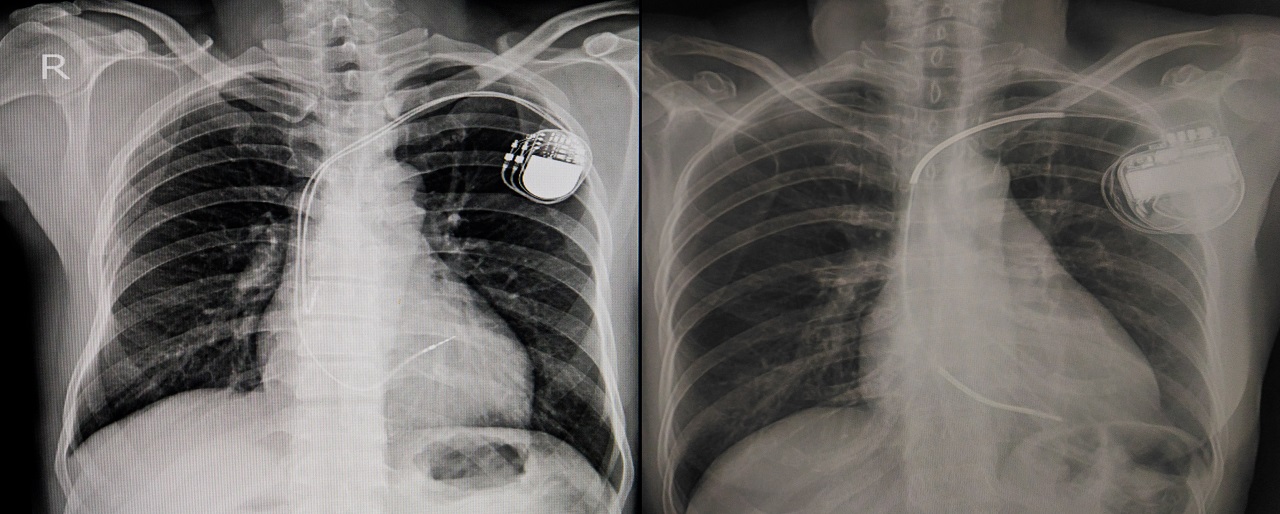

X-ray revealing placement of permanent pacemaker

This device has been scientifically engineered by a number of medical professionals to help mimic the heart’s natural electrical functions. It has two main functions for the device to run properly. The first is the pulse generator. This small metal container houses the battery and the electric circuits that regulate the pulses sent to the heart. Next are the leads and electrodes. These are one to 3 insulated wires that are placed in the chambers of your heart to deliver the electrical pulses that adjust the heart rate.